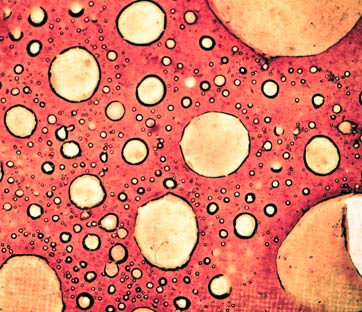

Certo, i vantaggi di questo nuovo approccio terapeutico non mancano. Immaginate un cecchino, un tiratore scelto, che colpisce senza margine di errore un bersaglio evitando il rischio di ferire la folla. La caratteristica dell’adroterapia, ambito disciplinare cui appartiene la protonterapia, è proprio questa. Si tratta di un tipo di radioterapia che utilizza particelle subatomiche pesanti al posto dei raggi X. Le più usate, oltre ai protoni, sono gli ioni carbonio. Caratteristica del trattamento è dunque di poter concentrare la dose in un volume ben definito (il tumore o la massa da irradiare) con una minore dispersione di radiazione nei tessuti sani circostanti. Gli ioni carbonio, in particolare, si dimostrano particolarmente efficaci in caso di tumori resistenti alle radiazioni convenzionali e anche ai protoni (la cui efficacia biologica è analoga a quella dei raggi X) per la loro capacità di determinare un danno maggiore a carico del Dna delle cellule tumorali.